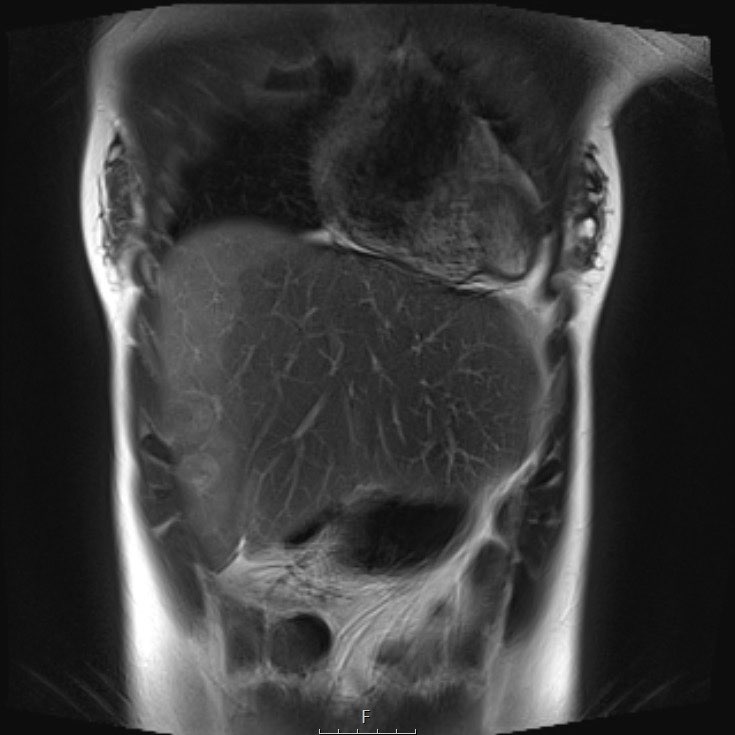

Same patient.

Đây là hình ảnh T1W axial có tiêm gadolinium với kỹ thuật xóa mỡ.

Hình ảnh cho thấy sự bao bọc của các mạch máu.

Lưu ý sự lan rộng của khối u ra phía sau động mạch chủ, đẩy động mạch chủ ra xa cột sống (mũi tên).